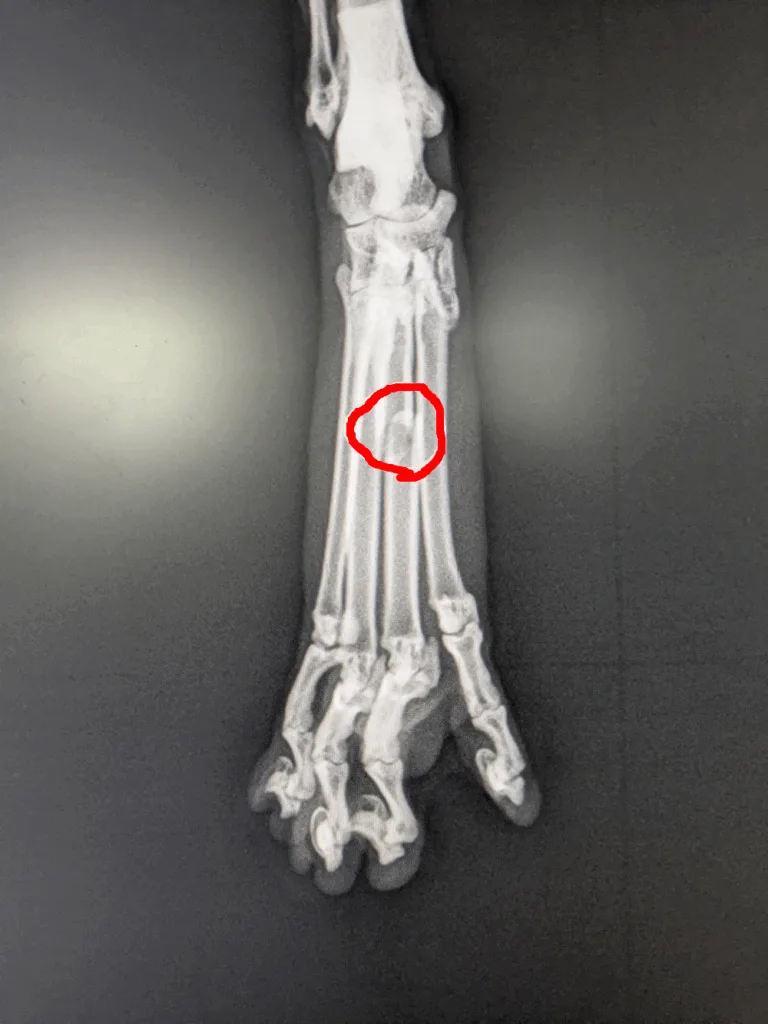

診断は基本的にレントゲン撮影が主となります。

赤い丸で囲んでいるところが骨折線です。

折れているのが1本で、骨どうしがずれていなければ外固定(ギブス固定)で良いのですが、本症例は折れた骨がずれて下に潜り込んでいたので、手術での整復が必要と考えました。